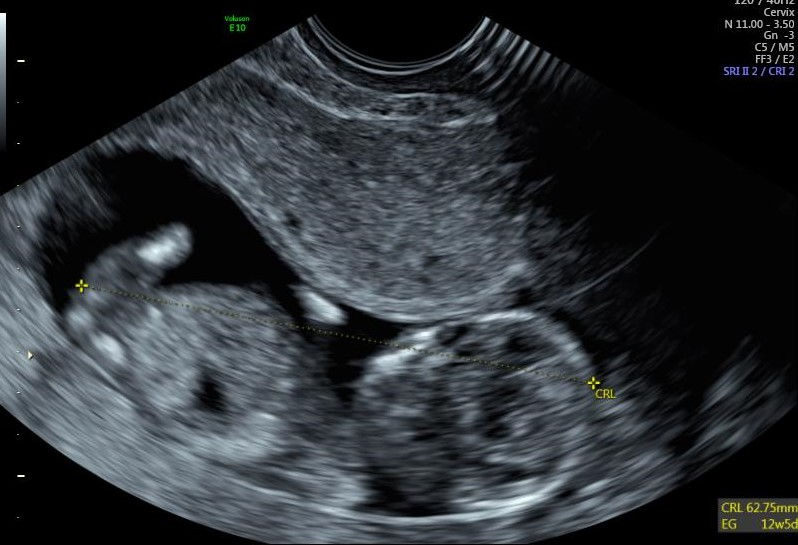

Amb la confirmació de l'embaràs, els futurs pares es troben davant una nova situació que els hi genera sentiments contradictoris i un munt de fantasies i ansietats que requeriran un temps per a ser elaborades. A més, si es dóna el cas que l'espera es dilati en el temps per causes biològiques alienes a la seva voluntat, aquestes fantasies i ansietats s'incrementen i n'apareixen de noves, relacionades amb el sentiment d'impotència i frustració que pot aparèixer. Un cop la viabilitat de l'embaràs està garantida, la parella començarà un procés psíquic –que acompanyarà el procés biològic de la mare i el nadó-, per anar fent-se càrrec d'aquesta nova situació i obrir un espai simbòlic que doni lloc a l'infant que aviat arribarà.